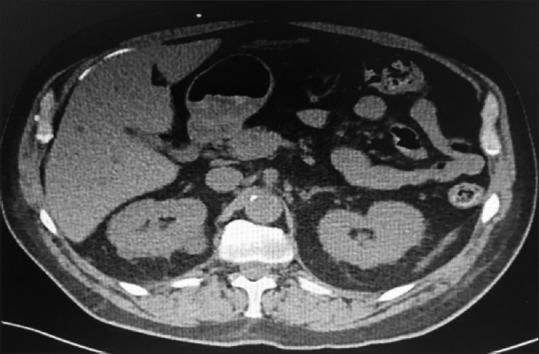

We describe an atypical case of VP shunt postoperative by normal pressure hydrocephalus. After well-documented proper positioning of the distal catheter into the intraperitoneal cavity, it protruded into the subcutaneous space. Even on a new documented satisfactory abdominal tomography, this catheter migrated back again to the subcutaneous tissue.

我们描述了一例常压性脑积水VP分流术后的非典型病例。在有充分记录证明远端导管正确置入腹腔后,它却突出到皮下间隙。即使在新的记录显示腹部断层扫描结果令人满意的情况下,该导管再次迁移回皮下组织。